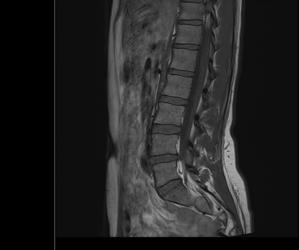

Sofand Skrevet 9. mars 2019 Skrevet 9. mars 2019 Er det noen innenfor faget som ser hva dette MR bildet av ryggen viser?

Skandinav Skrevet 10. mars 2019 Skrevet 10. mars 2019 Bildet er ikke det tydeligste, men ser ut som en gammel prolaps mellom L4 og L5.

Sofand Skrevet 10. mars 2019 Forfatter Skrevet 10. mars 2019 Bildet er ikke det tydeligste, men ser ut som en gammel prolaps mellom L4 og L5. Tusen takk for svar! Sier disse bildene noe mer kanskje?